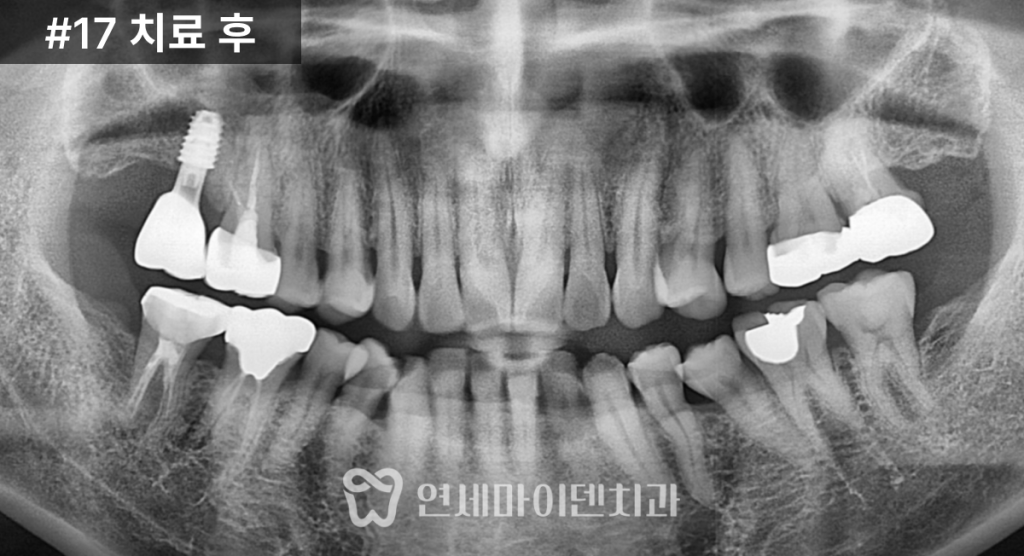

검사 결과,

17번 치아는 뼈 높이가 전반적으로 낮았고

상악동 점막이 두꺼워진 상태였습니다.반면 16번 치아는

깨지고 염증이 있었지만

정밀 평가 결과

충분히 살려볼 수 있는 여지가 있었습니다.이에 따라 치료 계획은 다음과 같이 세웠습니다.

- 16번 치아: 신경치료 및 잇몸치료를 통한 보존

- 17번 치아: 상악동 거상술을 동반한 임플란트 식립

저작 기능을 회복했습니다.치료 결과와 경과

치료 후 CT와 임상 사진에서

임플란트의 안정적인 고정 상태와

교합 회복을 확인할 수 있었습니다.앞쪽 16번 치아는

2년 이상 안정적으로 유지되고 있으며,뒤쪽 17번 임플란트 역시

상악동염 재발 없이